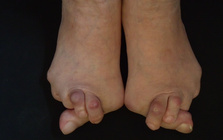

靴の健康被害、外反母趾。

外反母趾の問題は痛みだけではありません。

その変形症状から多くの身体の不具合と

ほかの症状、病気を発症させてしまう方、